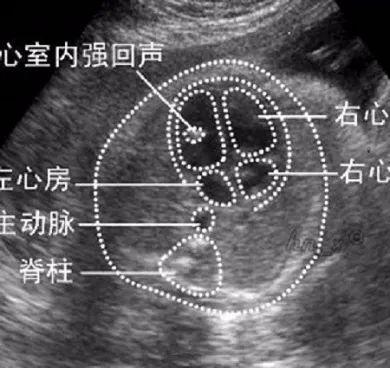

产前检查时b超检查发现胎心室内有亮点,是b超检查的常见表现,也是产前检查的软指标。强心室光斑是一种异常的胎心结构。原因不明。正常和异常胎儿都可能出现。它发生在正常胎儿的1%到5%之间。原因既有理性的,也有病理性的。

孕期b超检查发现单个胎儿心室亮点,多数情况下是生理性的。它只是对超声检查时所见图像的描述,也可能是成像操作时平面反射的结果。胎儿亮点本身并无特异性,不代表胎心畸形,也不能作为胎心异常的诊断指标。

心脏内的强光点多由乳突肌钙化或心室内瓣膜腱索增厚引起,相当于乳头肌或腱索内的点状孤立性局灶性回声,其回声强度与胎儿骨相似,故图像表现为强光点。

一般来说,胎儿左心室的亮点比较常见,而右心室的亮点不太常见。一般无明显临床意义。随着胎儿在宫腔内的快速生长发育,大部分胎儿心脏内的亮点会消失,少数会持续到出生后,超声心动图可以检测到。